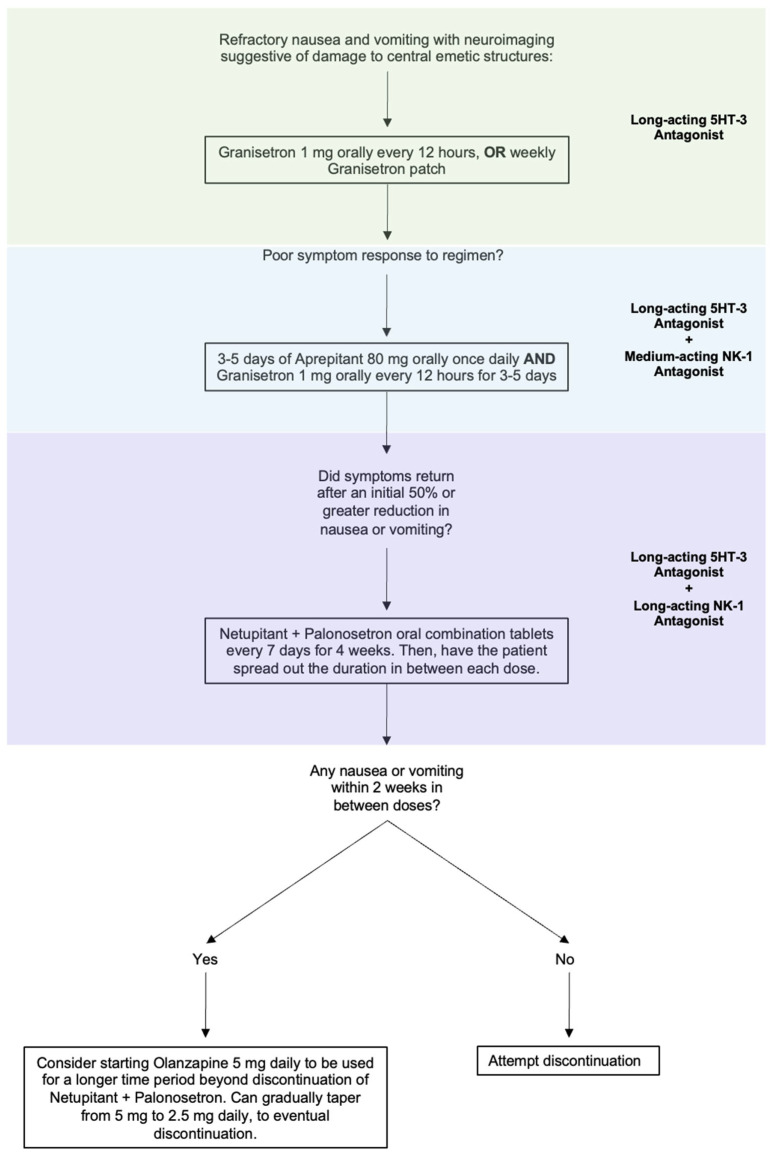

Intractable nausea and vomiting due to a CNS lesion or injury can be approached by combining 5-HT3 blockers with an NK-1 receptor antagonist. As most patients will have tried and failed ondansetron, likely in combination with D2 blockers, longer-acting medications reserved for use in CINV would be the next agents to trial. Granisetron orally every 12 h is a reasonable first step to see if a longer acting 5HT-3 antagonist improves the nausea and vomiting. The granisetron patch is also available as a weekly therapy, which may be an option in the right clinical circumstances. If long-acting 5HT-3 antagonism is unsuccessful, moving to combined therapy would be the next step. Given the off-label nature, cost, and unknown safety profile of the following medications in combinations outside of their indicated uses, we recommend a sequential therapeutic trial to target the symptoms that the patient is experiencing (Figure 2).